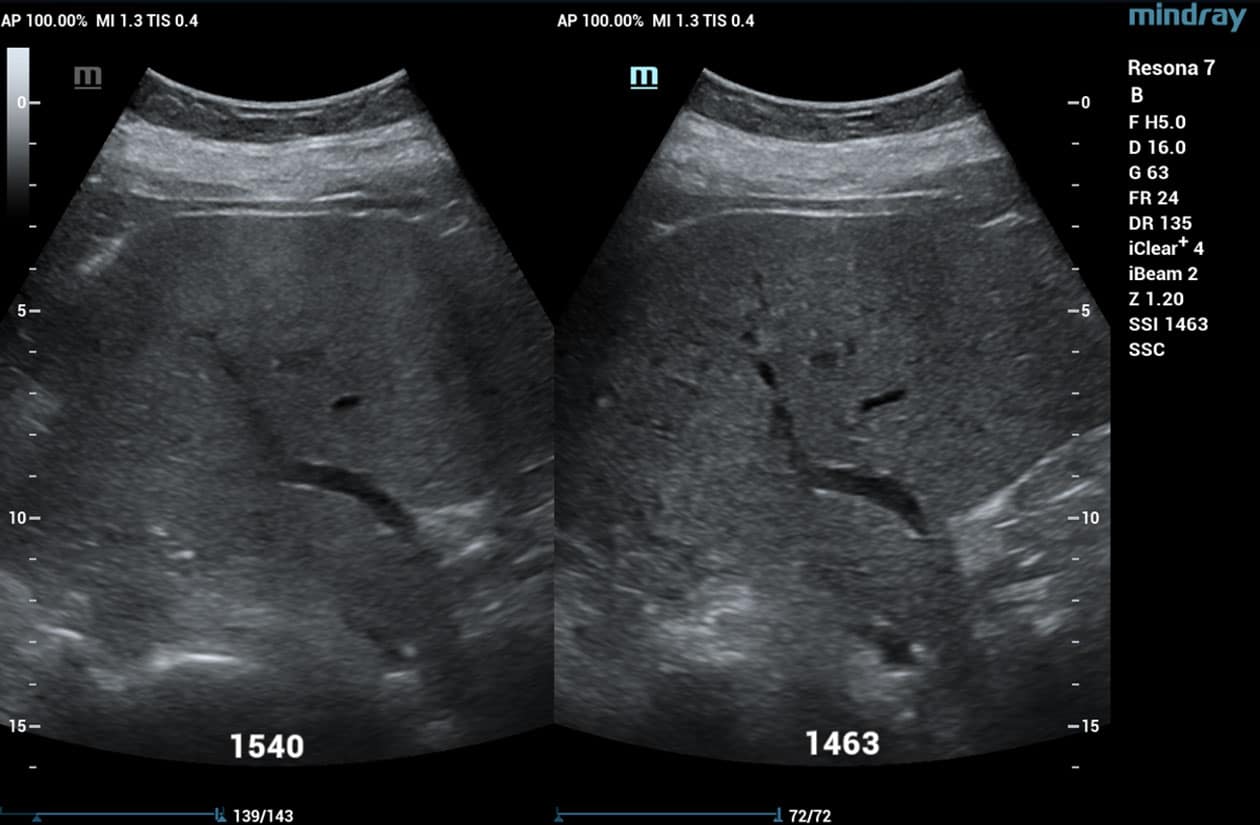

HD Scope

HD Scope is an advanced B-mode image processing technique that focuses additional imaging resources within a specified region of interest (ROI), analyzes the received channel data in unique ways, and applies various filtering and processing algorithms. This results in enhanced contrast resolution within the ROI based on the acoustic characteristics of varying tissue types.